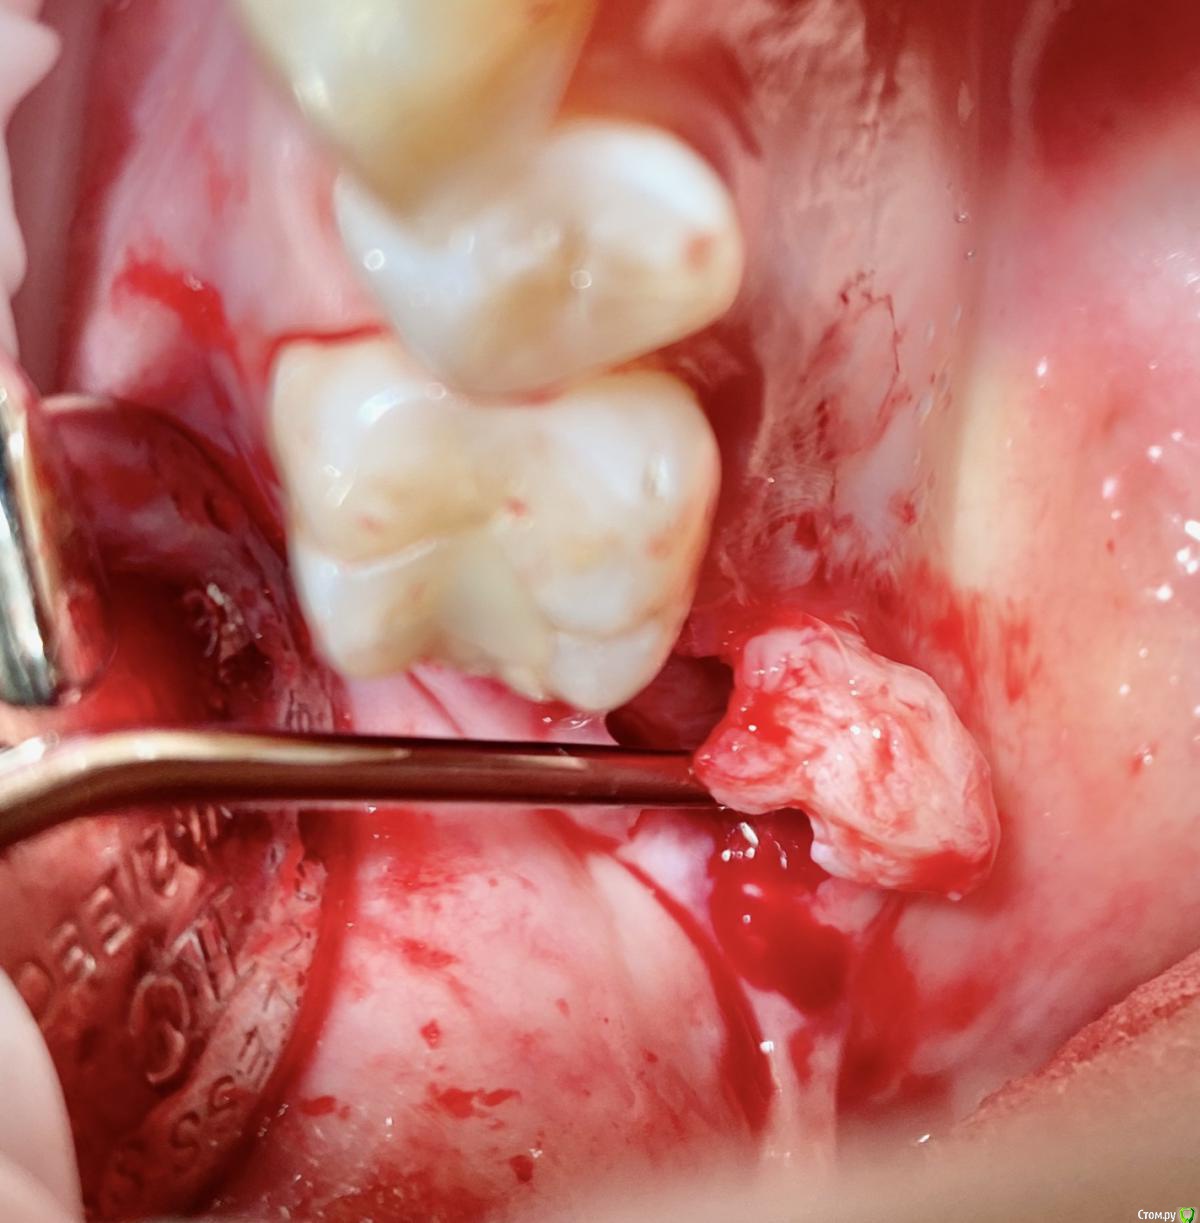

колесников Опубликовано 9 сентября, 2020 Поделиться Опубликовано 9 сентября, 2020 Т.е. на месте кривой это подслизистое отслоение, а где овал - это бугор, который нужно ротировать? овал-это бугор который мы видим и зачастую используем. Кривая-это бугор который можно забрать под слизистой. Конечно чем дальше к периферии ,тем его качество падает ,но он есть. Делаете поверхностный разрез ретромолярно,расщепляете,выделяете лоскут -заплатку,обрезаете её вестибулярно,дистально. Небно отступаете от края мм на 5 и проводите разрез до дистального края 7ки. Отделяете от основания. У вас получается заплатка на ножке. Перекидываете ее на гребень и вносите под вестибулярный край лоскута лунки,фиксируя матрасным швом. Далее придавливаете ножку перекидными швами небно-вестибулярно (ножек не прошиваем,только прижимаем). 3 Ссылка на комментарий

колесников Опубликовано 11 сентября, 2020 Поделиться Опубликовано 11 сентября, 2020 Перемещение бугра для закрытия лунки. Вестибулярно прикрепленную не смещаем. Вестибулярно компактной пластинки нет 9 Ссылка на комментарий